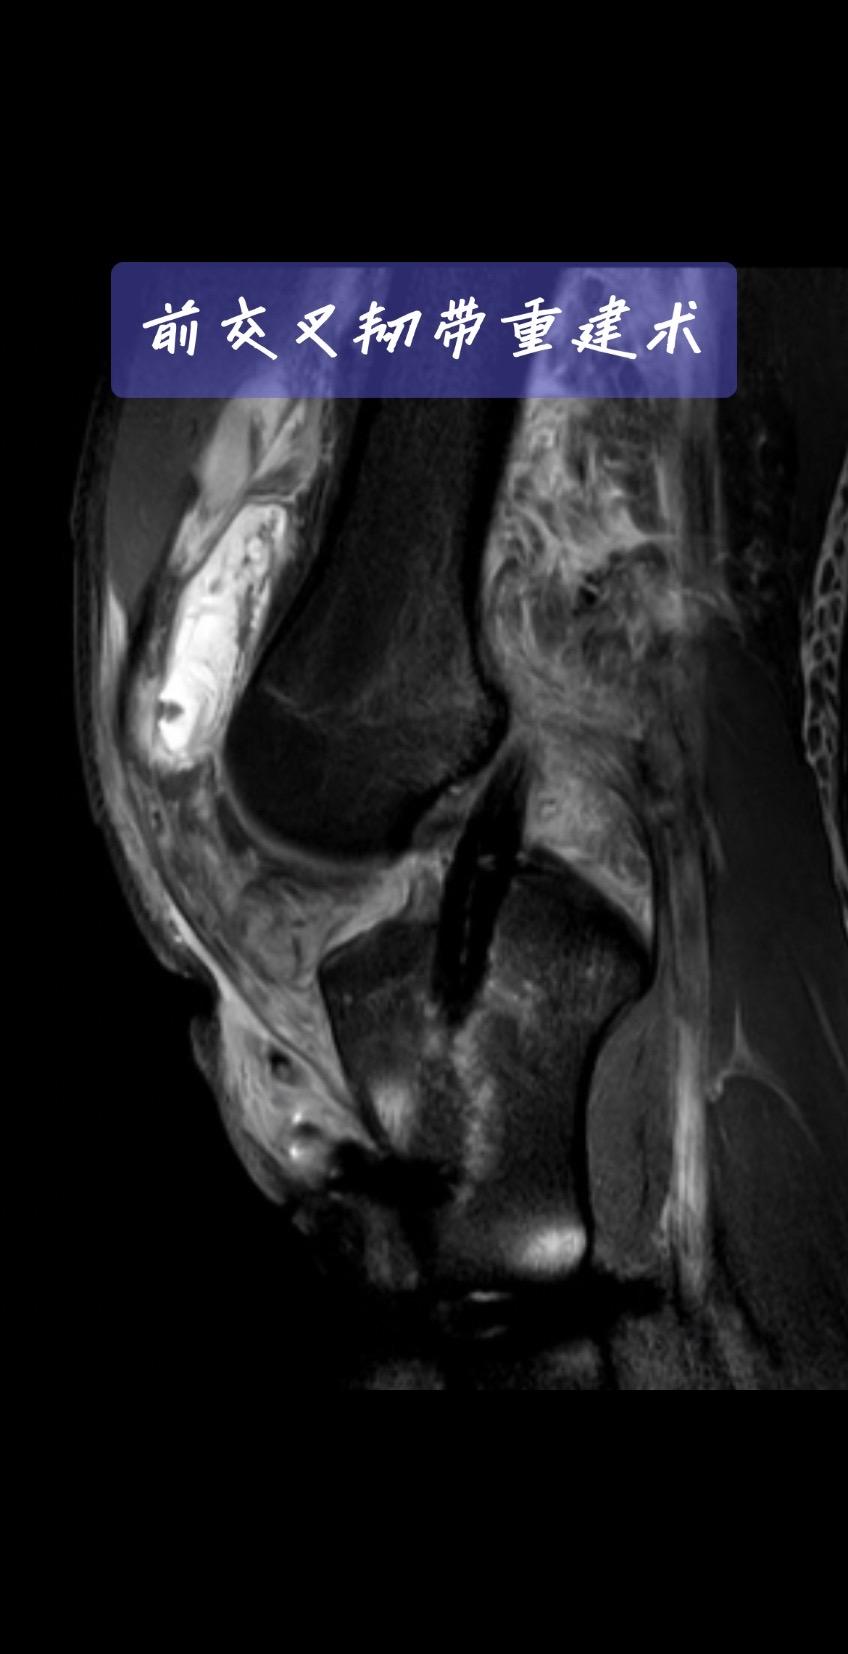

前交叉韧带重建。一台成功的前交叉韧带重建,关键在于“精准”二字。术后CT、MRI复查,就是我们医生的“成绩单”。前交叉韧带重建 运动医学 膝关节术后 骨科医生 医学科普